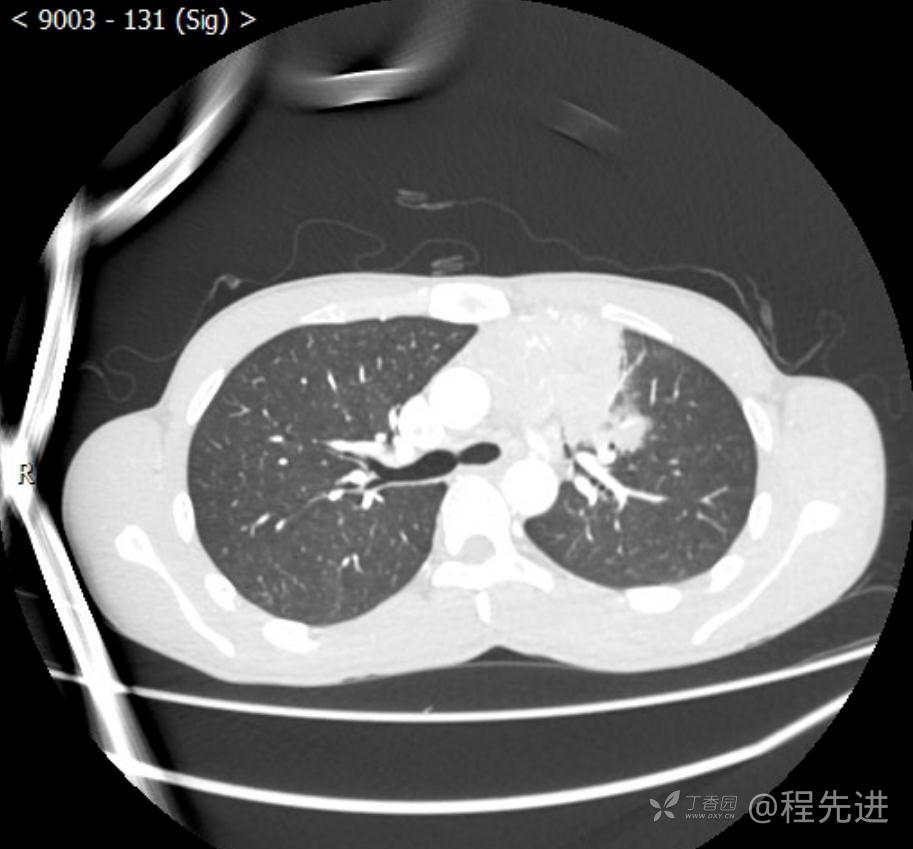

主诉:反复咳嗽1月,发现“纵隔”占位半月,乏力10余天。

现病史:患者1月前无明显诱因出现咳嗽,以夜间为著,伴有少量白痰,无发热,无胸痛、咯血,无痰中带血,未予重视,半月前外院行胸部CT检查发现“左前上纵隔”占位,未予进一步检查及治疗。近10余天自觉乏力,逐渐加重。